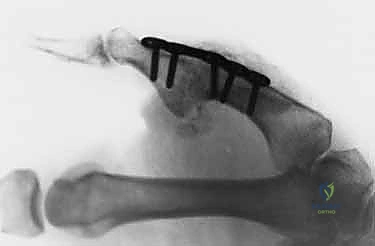

العلاج الجراحي: الدقة والاحترافية مع أ.د. محمد هطيف

عندما تفشل العلاجات التحفظية، أو في حالات التمزق الكامل (الدرجة الثالثة)، الكسور الانقلاعية الكبيرة، عدم الاستقرار المزمن، أو وجود "آفة ستينر"، يصبح التدخل الجراحي الخيار الوحيد لإنقاذ وظيفة اليد.

يُعد الأستاذ الدكتور محمد هطيف رائداً في جراحات اليد الدقيقة في اليمن. باستخدام تقنيات متقدمة مثل الجراحة الميكروسكوبية والتدخلات طفيفة التوغل، يتم تحقيق نسب نجاح تضاهي أفضل المراكز العالمية.

| طبيعة التدخل | جبيرة مخصصة (Spica)، أدوية، علاج طبيعي. | خياطة الأربطة، استخدام خطاطيف عظمية (Anchors)، إعادة بناء الأربطة. |